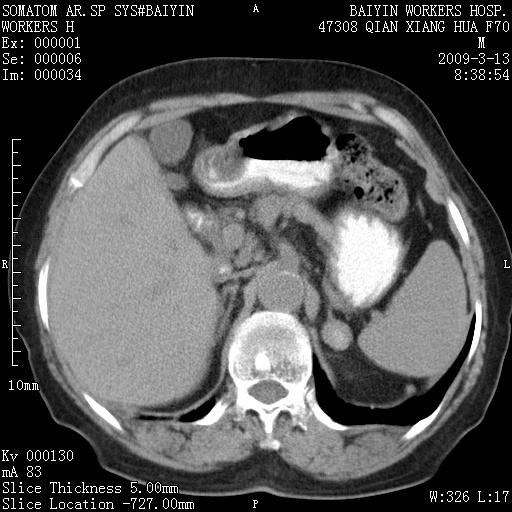

标题: CT18651:左肾上腺占位,请会诊!

女,70岁,体检发现。

左肾上腺腺瘤

左侧肾上腺结节状软组织密度影;考虑肿瘤(肾上腺腺瘤?转移瘤?)。

左侧肾上腺占位,腺瘤?不除外转移。

左侧肾上腺占位,腺瘤可能。

左侧肾上腺占位,考虑腺瘤可能。